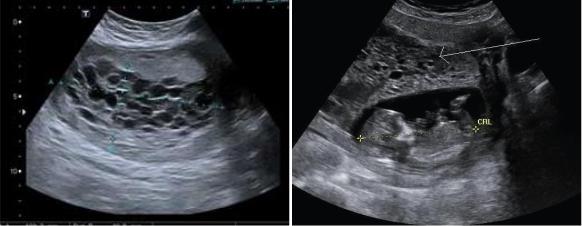

При ультразвуковом исследовании матки при полном пузырном заносе могут быть выявлены его элементы в виде гомогенной мелкоячеистой массы и отсутствие плода (рис. 6-а), а также наличие лютеиновых кист яичников.

а) б)

Рис. 6. Пузырный занос (сонограммы): а) полный (ячеистая масса в полости матки); б) частичный: между маркерами – погибший плод, стрелкой указан пузырный занос.

При частичном пузырном заносе на сонограммах могут выявляться деформированные элементы плода (эмбриона), оболочек, плаценты, амниотическая полость, ретрохориально определяется участок ячеистой структуры (пузырный занос), в котором при цветовом допплеровском картировании визуализируются области повышенной васкуляризации, а васкуляризация неизмененных ворсин хориона исчезает вслед за гибелью эмбриона (рис. 6-б).